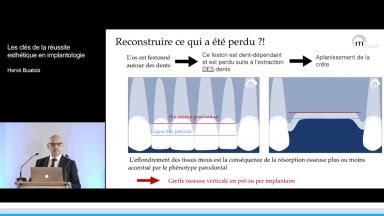

Le point central est l’objectif prothétique puisque la position tridimensionnelle de l’implant placé lors de la phase chirurgicale est dictée par le résultat prothétique souhaité. Ainsi, l’orateur revient sur les critères fondamentaux à respecter pour positionner idéalement l’implant par rapport aux dents adjacentes et à la crête osseuse résiduelle. Ensuite, des méthodes de correction osseuse, gingivale et prothétique visant à améliorer le résultat final sont présentées. La classification retenue est basée sur la sévérité de la perte de volume des tissus osseux et gingivaux adjacents à l’édentement, avec pour objectif d’obtenir un résultat prothétique harmonieux.